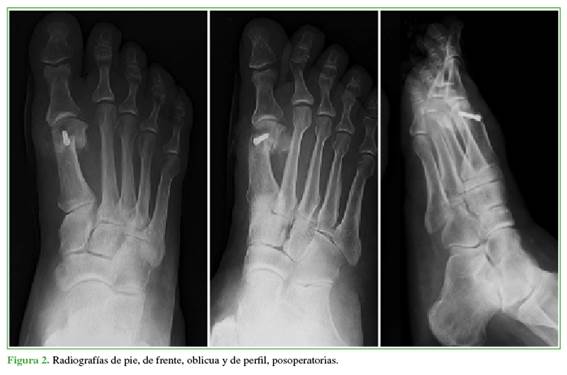

A todos los pacientes se les tomaron radiografías anteroposterior, latero-lateral con apoyo y oblicua de pie antes de la cirugía (Figura 1), en el posoperatorio (Figura 2) y a los 18 meses de la intervención (Figura 3) para establecer el ángulo intermetatarsiano (IM), el ángulo del hallux valgus (HV), el ángulo articular metatarsiano distal (AMD), la congruencia de la articulación metatarsofalángica, el ángulo interfalángico, la altura del M1, el grado de deformidad, el grado de lesión, la movilidad articular del hallux, la presencia de dolor, y para planificar la cirugía.

Se ubicó a los pacientes en decúbito supino luego de la anestesia raquídea. Se colocó un manguito hemostático en el muslo. Se realizó un abordaje medial de hallux clásico de 3 a 5 cm, la cápsula se incidió en Y para luego acceder al M1 al cual se le realizó una queilectomía dorsal y una buniectomía con sierra oscilante. Se marcó el centro de rotación del M1 que sirve para practicar los cortes. El primero se efectuó desde el punto en el centro de rotación de la cabeza del M1 en dirección plantar a 45° en dirección proximal. Los cortes siguientes se efectuaron en la unión de la cabeza y el cuello del M1, perpendicular a este, de lado a lado. El siguiente corte se realizó 1-3 mm distal a este, dejando un escalón lateral no superior al 25% del ancho total del metatarsiano. La tabla ósea resultante se utilizó como injerto aditivo en el corte plantar. La osteotomía es intrínsecamente estable. Igualmente se fijó con un tornillo doble rosca de 3 mm (Figura 4). Se utilizó un intensificador de imágenes para corroborar la correcta posición de la osteosíntesis.

Se tomaron radiografías del pie de frente, oblicua y de perfil en el posoperatorio inmediato para evaluar una posible pérdida de la reducción. Se consideró un resultado radiográfico definitivo a los 18 meses o más de la cirugía.